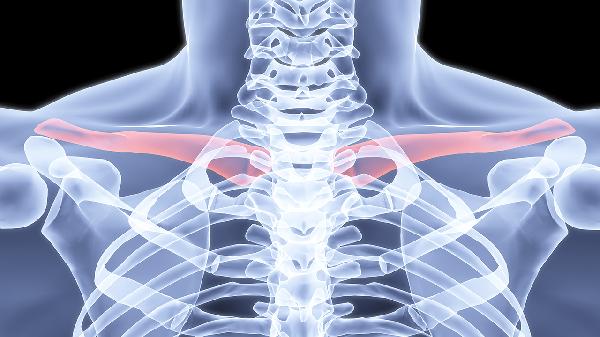

骨折端在非解剖位置形成纤维性连接,表现为局部隆起或肩部不对称。畸形可能压迫血管神经或影响关节功能。矫正需手术截骨重新固定,必要时联合自体骨移植。